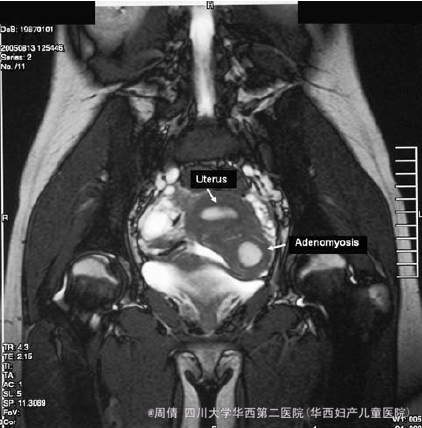

院外超声提示两个子宫腔,怀疑是双角子宫,但是左角梗阻 MRI提示子宫异常,子宫左前壁内膜内有一肿块 CA125水平正常

行诊断性腹腔镜,可见子宫右侧有一肿块,认为可能是阔韧带肌瘤或者退化的子宫角 手术切除肿块 切开肿块,其内有深褐色的内容物 宏观可见一个直径为3.5cm的不规则灰白色结节内,有一个直径为1.5cm的出血灶 病理提示囊腔为子宫内膜腺体和基质,提示为子宫内膜异位囊腔 术后患者痛经好转

卵巢子宫内膜异位囊肿形态上以圆形、椭圆形多见。由于其具有强烈的穿孔、破裂及出血粘连特性,出血时间的先后不等,血液刺激产生反应性的纤维组织增生。超声可协助盆腔肿块定位,区分卵巢囊性、囊实相间或实质性肿块。卵巢子宫内膜异位囊肿的MRI信号可表现为多种信号变化,其信号因出血的新旧、液态或固态血,纤维组织等改变。 其实这个病人术前怀疑是双角子宫,没诊断出是子宫内膜异位,临床上要术前诊断EMT还是主要结合症状来的。